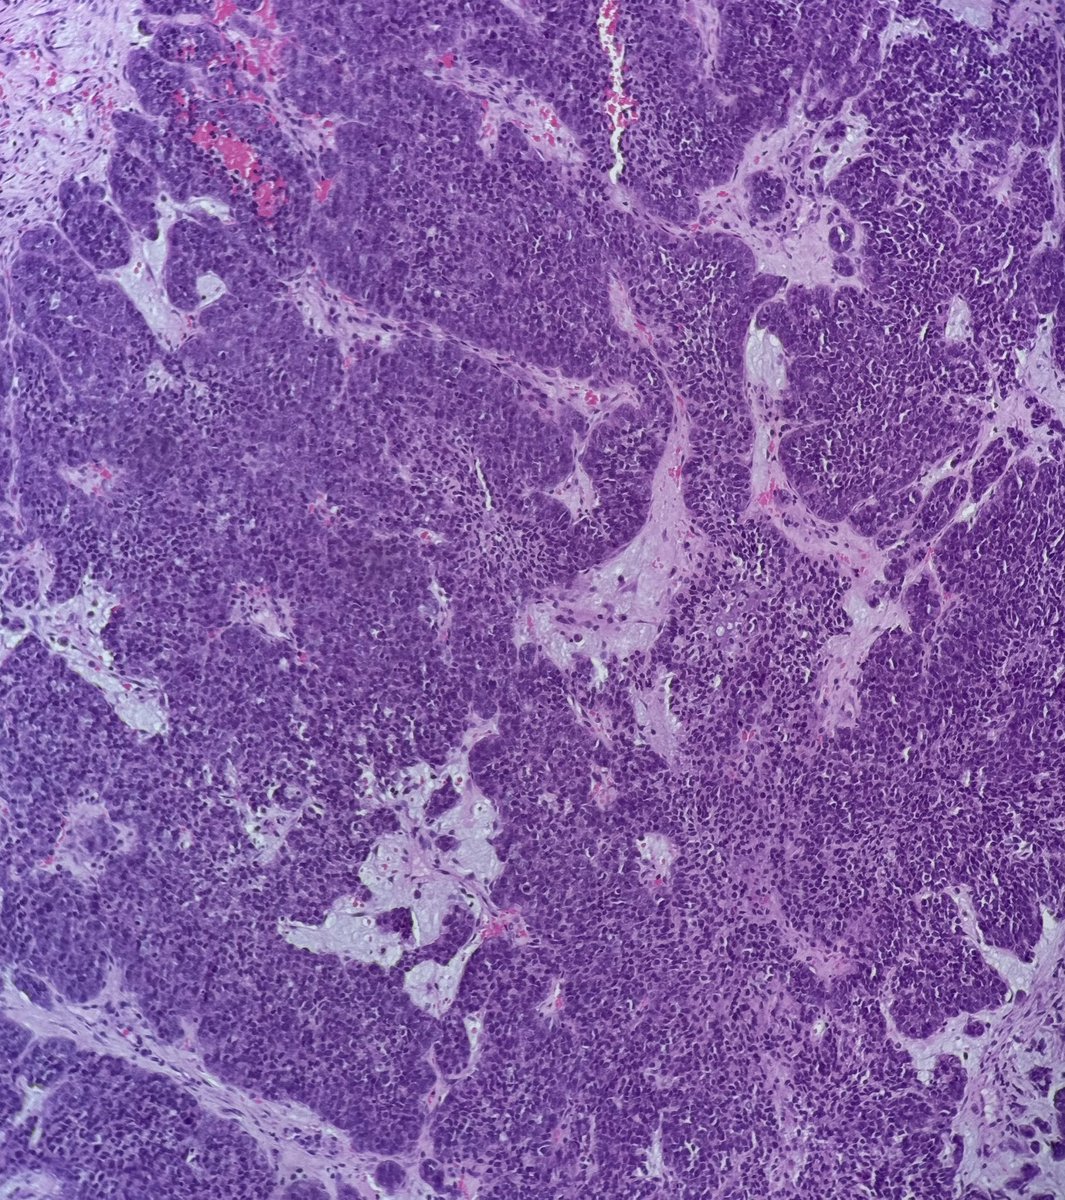

59-year-old woman with a destructive sinonasal tumor. Liver and iliac mets on CT. Biopsy performed (more pics below). Diagnostic opinions are welcome! #pathology #PathTwitter #surgicalpath #oralpath #entpath